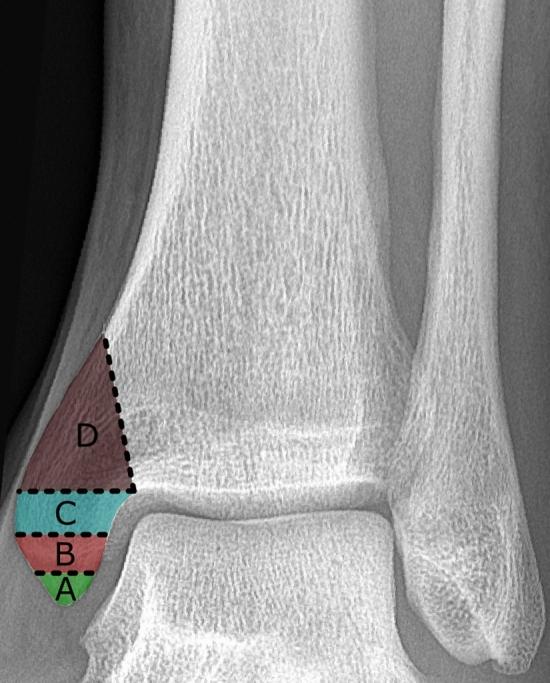

Different classification systems have been developed for ankle fractures. In recent years, the posterior malleolus has gained in importance and led to computed tomography (CT)-based classification systems. The aim of the study was to analyse their reliability, fracture patterns and influence on treatment strategy.

Patients with a trimalleolar ankle fracture treated between 2011 and 2020 with preoperative radiographs and CT images were included. The blinded images were independently classified by three reviewers according to the AO/OTA, Herscovici, Bartoníček, Mason and Haraguchi classifications. The interobserver reliability was calculated by Fleiss' kappa (κ). CT images were analysed to determine the dimensions of the posterior malleolus fragments. Patient registries were reviewed regarding the treatment data.

A total of 193 patients were included. The AO/OTA classification showed almost perfect inter- and intraobserver reliability (Fleiss' κ = 0.86, 95% CI 0.82-0.90). Regarding the posterior malleolus, the Bartoníček classification demonstrated the highest reliability (Fleiss' κ = 0.78, 95% CI 0.73-0.83). The Herscovici classification only reached moderate reliability for medial malleolus fractures (Fleiss' κ = 0.59, 95% CI 0.54-0.65). There was a trend towards direct fixation of the posterior malleolus in the last 3 years of the observation period (OR: 2.49, 95% CI 1.03-5.99).

In trimalleolar ankle fractures, the AO/OTA classification is a reliable system to characterize the type of fracture, but it fails to provide solid information about the posterior malleolus. Nowadays, treatment recommendations for trimalleolar ankle fractures focus on the configuration of the posterior malleolus; therefore, the results of this study advocate the use of the Bartoníček classification as a reliable tool to guide treatment.